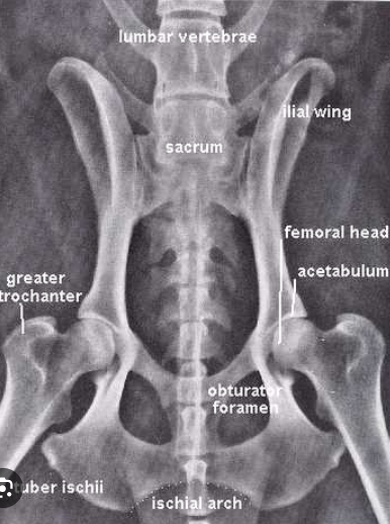

Review sacral anatomy.

A